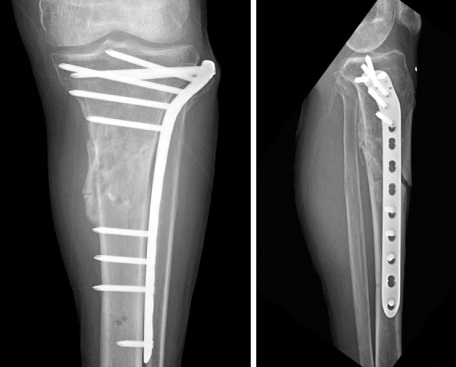

Bow legs, also known as genu varum, is a condition where the legs appear bowed outwards when standing. This condition can cause discomfort, pain, and even difficulty walking. In severe cases, surgery may be required to correct the alignment of the legs. In this article, we will discuss the causes, symptoms, and treatment options for bow legs, including the various surgical procedures available.

The treatment options for bow legs will depend on the severity of the condition and the underlying cause. Some common treatments include

The treatment options for knock knees will depend on the severity of the condition and the underlying cause. Some common treatments include